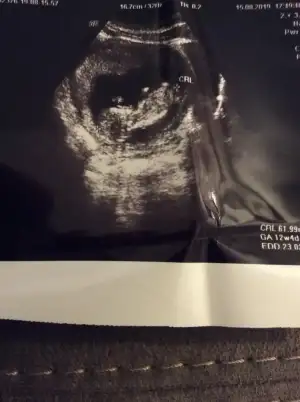

Bence erkekMerhaba arkadaşlar. Yeni bir görüntüyle geldimtahminde bulunur musunuz ?

Erkek gibiMerhaba arkadaşlar. Rica etsem tahminde bulunabilirmisiniz. Şimdiden teşekkürler :) Eki Görüntüle 2298870

Merhaba arkadaşlar. Rica etsem tahminde bulunabilirmisiniz. Şimdiden teşekkürler :) Eki Görüntüle 2298870

12+2 deyizİlk usg de kafa şekline erkek diyorum kaç haftalık burda 11 yada 12 hafta olmalı nub için

11 haftalik malesef bask usg yokNub görünmüyor başka usg varmı kaç haftalık 11 yada 12 hafta olmalı